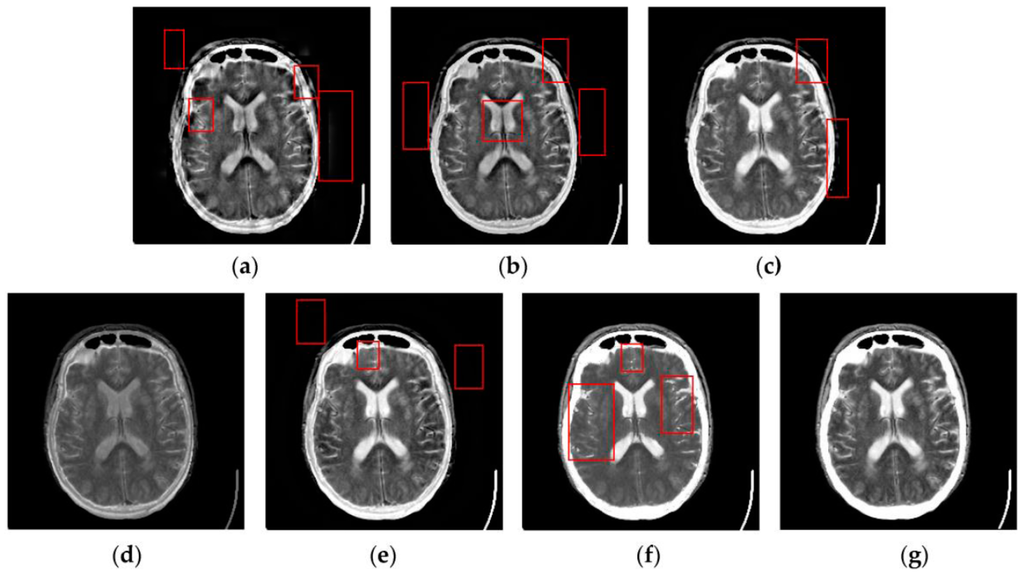

4.2. Visual Comparisons of Fused Results